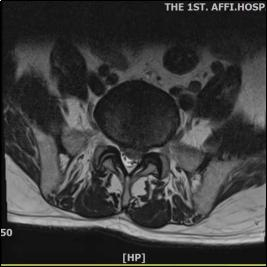

疼痛科主任舒雅接诊后,首先对王大叔进行查体等一系列检查,发现王大叔腰椎生理曲度变浅,腰部肌肉痉挛性紧张,腰3-4、腰4-5、腰5-骶1棘间及棘旁压痛(+),伴左下肢后外侧明显放射痛至足底部;左侧梨状肌压痛,伴左下肢明显放射痛,左小腿外侧及足背部、足底皮肤感觉减退,左侧直腿抬高试验10°,VAS 评分 8—9分,腰椎MRI显示突出物超出椎管矢状位中线的50%,属于巨大型腰椎间盘突出症。

结合腰椎MRI及患者症状,王大叔确诊为巨大型腰椎间盘突出症同时伴有腰椎椎管狭窄。